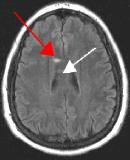

By turning CSF dark, bright periventricular lesions such as MS plaques become much more conspicuous. Fig. 1 shows a typical T2-weighted axial image of the brain in which CSF in the ventricles appears bright. A lesion on the right is present (red arrow) that is also bright similar to CSF. Fig. 2 is a corresponding FLAIR image showing an obvious bright MS plaque (white arrow) against a background of dark CSF and gray parenchyma with additional more subtle lesions.